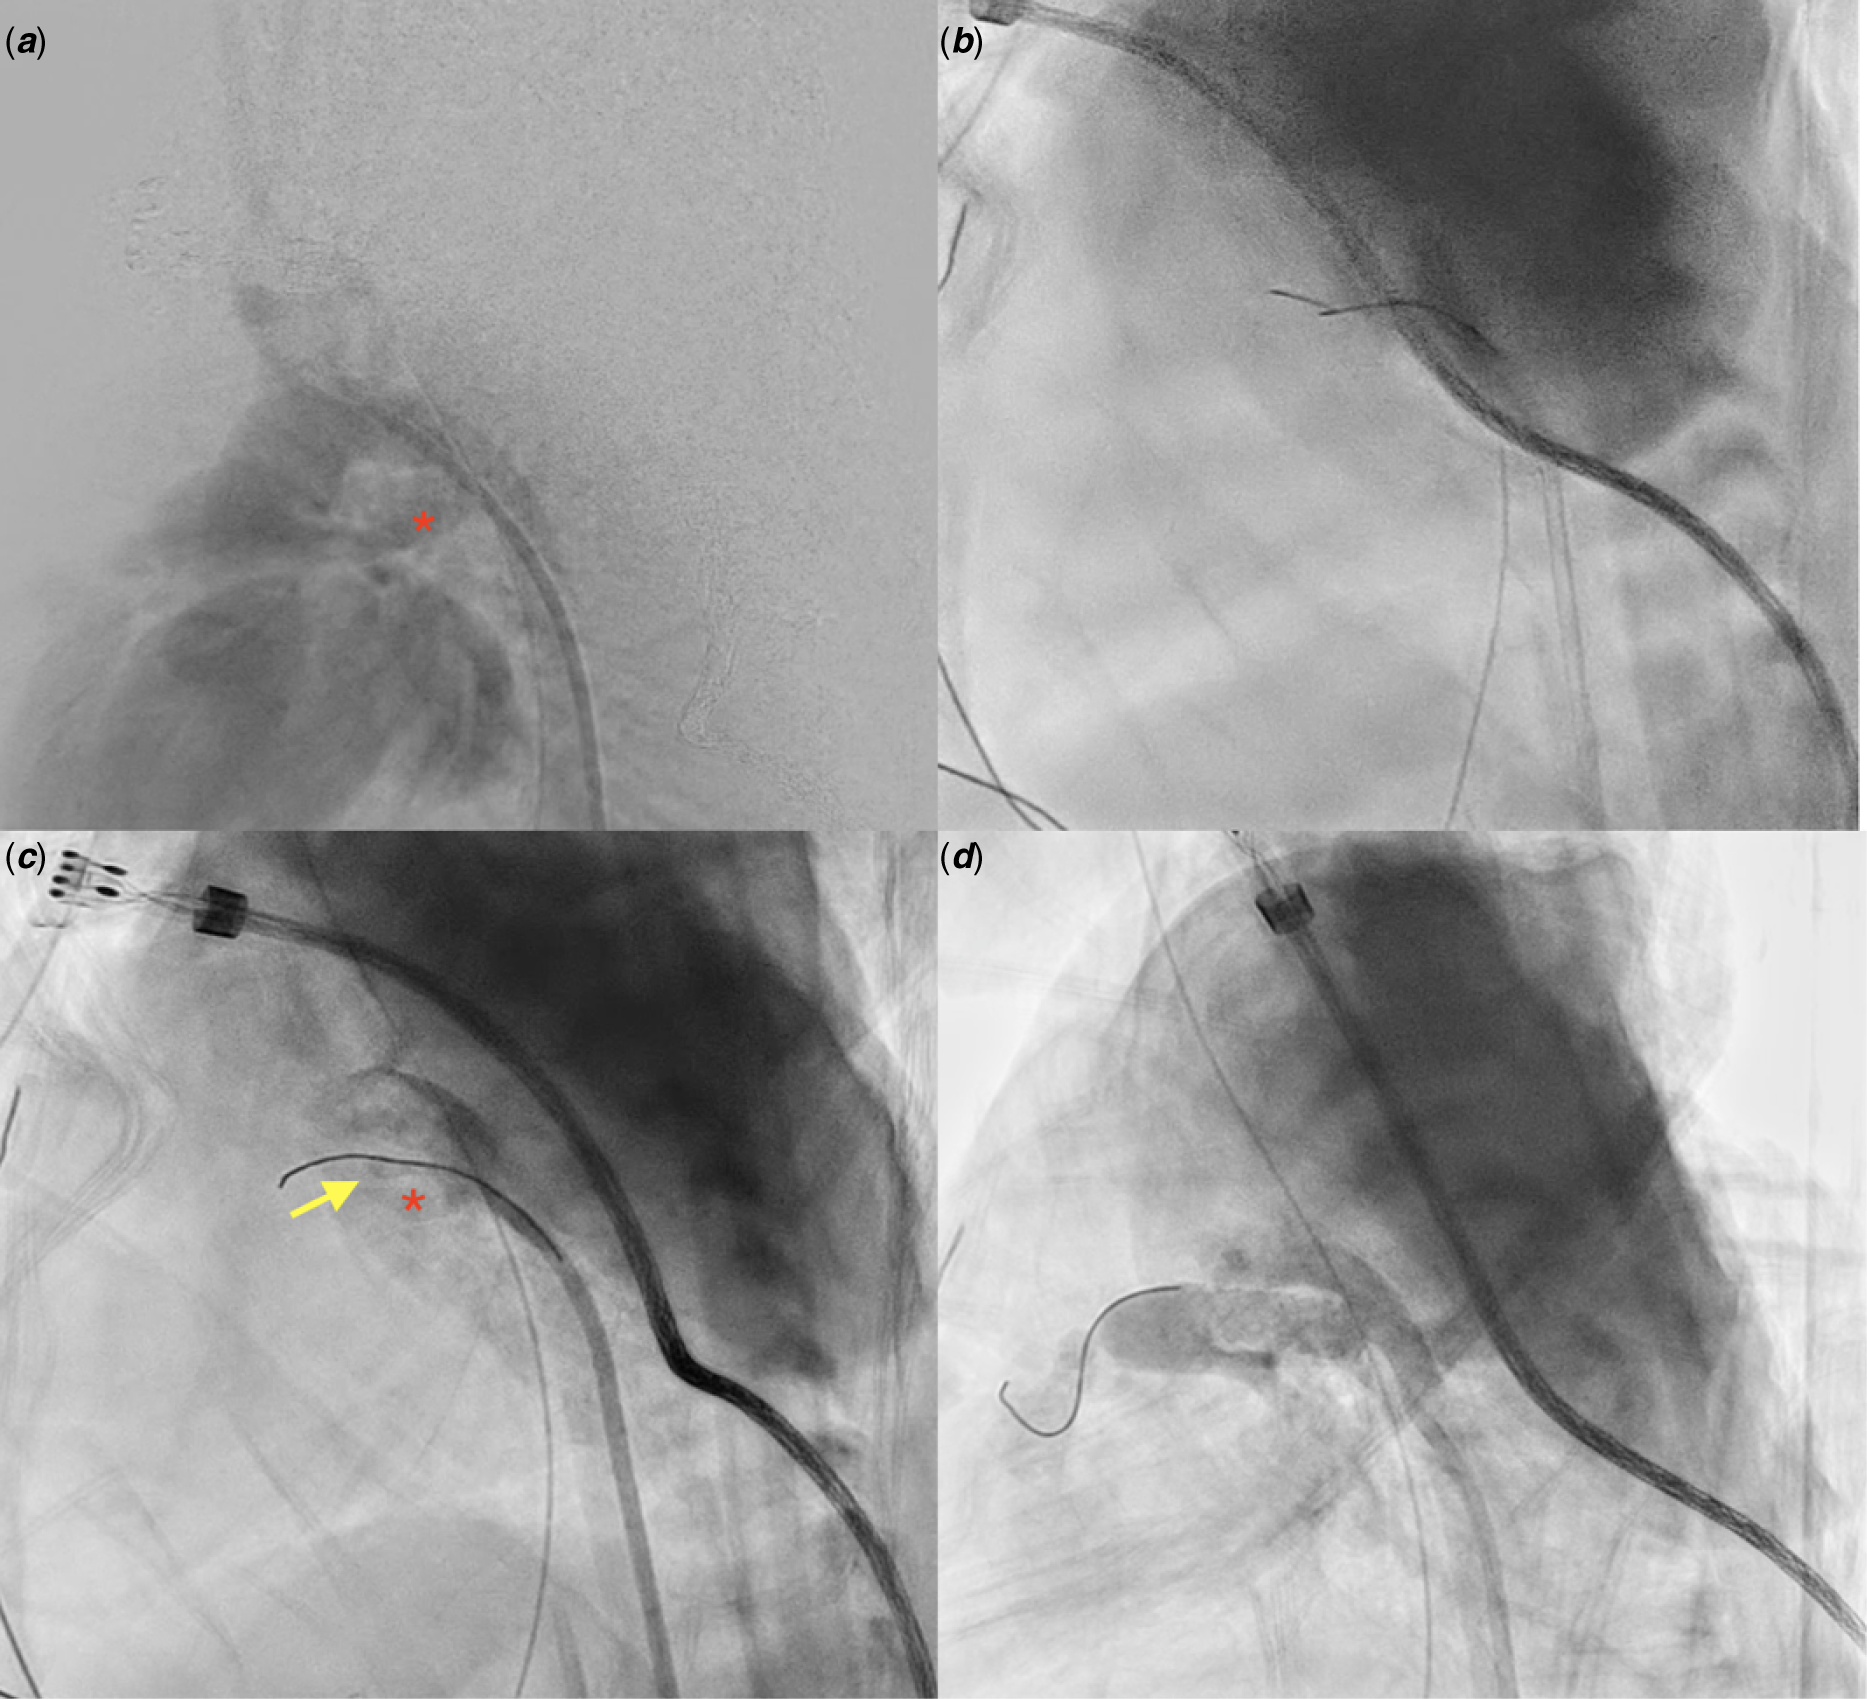

A newborn (gestational age 37 + 5 days, birth weight 2676 g) was found to have cyanosis (pulse oximetry 75%) upon birth. Echocardiography resulted in diagnoses of pulmonary atresia with intact ventricular septum, right ventricle hypoplasia, and patent ductus arteriosus. Continuous prostaglandin E1 was administered immediately. CT angiography confirmed the diagnosis. Transcatheter valvotomy with sequential balloon valvuloplasty was performed at 7 days old. Through the femoral vein approach, a 0.014-inch wire (percutaneous transluminal coronary angioplasty guide wire, Sion) was advanced through the Judkins right guiding catheter to the right ventricle outflow tract, and then a microcatheter (Excelsior) was introduced to the right ventricle outflow tract as a supporting system. Pulmonary valvotomy was performed using coronary guidewire (Conquest Pro 8-20 wire) penetration, and then sequential balloon valvuloplasty was conducted. Saturation was improved to pulse oxymetry 90% by the procedure. Nevertheless, desaturation occurred when prostaglandin E1 administration was tapered. Recatheterization for patent ductus arteriosus stenting was performed at 20 days old. Prostaglandin E1 was discontinued before the procedure. Through the femoral artery approach, the 0.014-inch floppy run-through wire with Judkins right catheter guiding was advanced from the descending aorta side of the patent ductus arteriosus (Fig 1a). The wire could not smoothly pass the patent ductus arteriosus to the pulmonary artery side, with mild distortion occurring at the tip of the wire upon fluoroscopy (Fig 1b, Video 1). Contrast extravasation was found (Fig 1c, Video 2). As ductal dissection was diagnosed, the wire was withdrawn. Desaturation was noted (pulse oximetry reduced to 60%). Repeat angiography showed severe ductal spasm. Readministration of PGE1 (20 ng/kg/minute) was performed. The haemodynamics were stable, and the saturation returned to 85% after 20 min of prostaglandin E1 infusion. Finally, a patent ductus arteriosus stent (Energy 5 mm × 18 mm) was implanted (Fig 1d, Video 3). After oversized patent ductus arteriosus stenting, the patient had tachypnea and pulmonary congestion on chest radiography was noted. Diuretics was used (Furosemide 2 mg/kg/day), and the symptom improved after medication and gradually resolved. No further cyanosis episodes occurred, and the patient was soon discharged. The diuretics was then tapered and discontinued 2 months after procedure.

Figure 1. (a) Angiography showed non-tortuous PDA with segmental narrowing on the PA side. Red asterisk: PDA. (b) PTCA-Sion wire was shown by fluoroscopy to be slightly distorted when passed through the PDA. (c) Angiography showed that the Sion wire was dropped in a false lumen, and contrast extravasation and ductal spasm were both found upon angiography. Red asterisk: PDA. Yellow arrow: false lumen. (d) Successful ductal stenting using a coronary stent (5 mm × 18 mm).